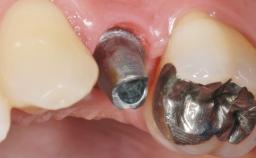

A 56-year-old female patient was referred to the clinic for the functional rehabilitation of her left mandible. The healthy, non-smoking patient presented with loss of retention of crown 35 due to secondary root caries. In addition, she had a single-tooth gap at site 36 with clearly discernible facial atrophy. The panoramic radiograph exhibited crowned teeth 35 and 37, both with a root canal filling. Tooth 37 showed a radiolucent area on the mesial aspect. Tooth 38 did not show any signs of pathology. Based on the clinical and radiographic findings, it was decided to remove root 35 and tooth 37, creating an extended edentulous space with three missing teeth. As requested by the patient, tooth 38 was left in place. The removal of both teeth was done without major flap elevation. The wound margins at site 35 had to be slightly elevated to remove the root remnant.

# of Implants 2

Type of Implants One-Piece

Prosthesis Type FDP